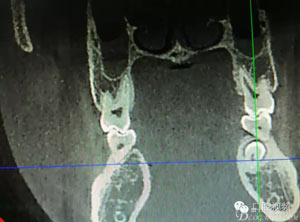

圖2.術(shù)前的CBCT,35移位至36、37之間的舌側(cè)。